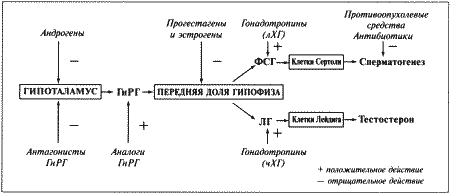

Стадия проэструса характеризуется развитием фолликулов под влиянием гонадотропных гормонов — лютеинизирующего (ЛГ) и фолликулостимулирующего (ФСГ), выделяемых передней долей гипофиза. Секреция этих гормонов регулируется гипоталамическим гонадотропинрилизинг гормоном (ГнРГ). У собак, так же, как и у других животных, вслед за пиком концентрации эстрадиола возникает (спустя сутки или чуть больше) пик концентрации ЛГ (фиг. 1.1). Таким образом, выброс ЛГ происходит всегда автоматически вслед за повышением активности фолликулов, вырабатывающих эстрадиол, и поскольку овуляция следует за возникающим без внешней стимуляции пиком концентрации ЛГ, ее называют спонтанной. Описанная ситуация разительно отличается от картины, которую можно наблюдать у кошек, для которых характерна индуцированная овуляция: у них выброс ЛГ и овуляция происходят вслед за коитусом. Насколько можно судить, у таких животных эстрадиол не способствует активации секреции ЛГ.

Повышение уровня ФСГ необходимо для стимуляции развития фолликулов и секреции эстрадиола, однако концентрация ФСГ в крови не достигает столь высоких значений, какие наблюдаются при пике ЛГ; это объясняют действием ингибина — белка, секретируемого фолликулами, который избирательно подавляет секрецию ФСГ Тем не менее ФСГ играет важную роль в созревании фолликулов и подготовке их к трансформации в желтые тела после овуляции. Начало трансформации фолликулярных клеток рассматривают как ключевой момент всего цикла, поскольку оно сопровождается преовуляторным повышением секреции прогестерона (фиг. 1.1), которое, по-видимому, играет ведущую роль в пусковом механизме овуляции и подтверждении эструса. Наблюдаемый у собак преовуляторный рост концентрации прогестерона нетипичен для других домашних животных, в частности для жвачных, у которых наступление эструса и овуляции происходит на фоне минимального уровня прогестерона. Однако преовуляторная концентрация прогестерона у собак все же относительно низка, и следует помнить, что назначение высоких доз прогестагенов в период проэструса вызывает отсрочку эструса и овуляции.